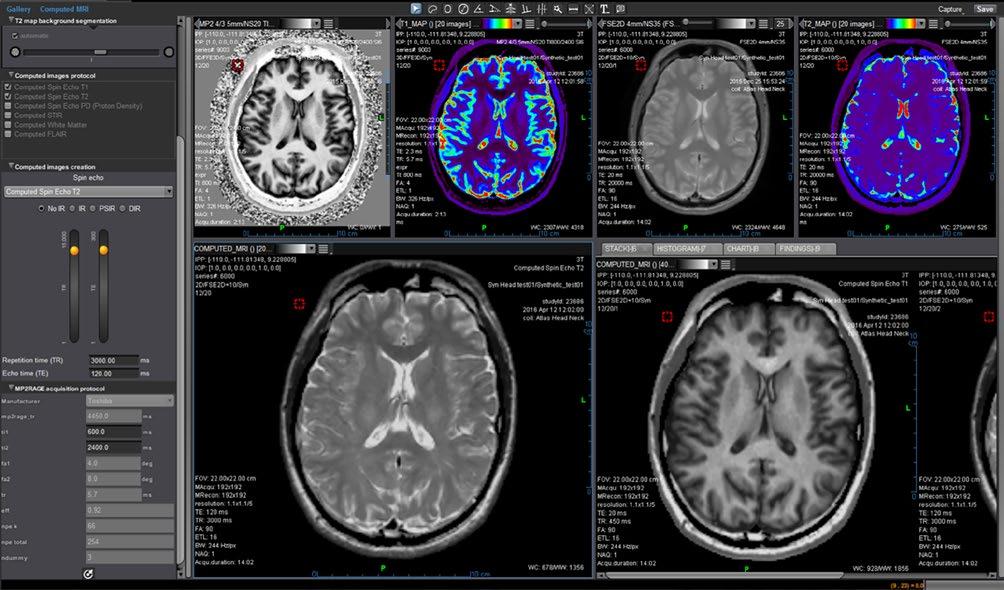

Artificial Intelligence to Boost MR Imaging Quality and Productivity

The power of AI is brought to routine MR imaging by Canon Medical’s Deep Learning Reconstruction (DLR) technology: Advanced intelligent Clear-IQ Engine (AiCE). AiCE is the world’s first fully integrated DLR technology for MRI.

One of the main challenges in MRI is finding the optimal balance between the signal-to-noise ratio (SNR) and image resolution. A higher spatial resolution

could improve visualization of structures, but when spatial resolution is increased, SNR drops. To regain SNR, typically scan times need to be increased, reducing patient comfort and decreasing throughput.

Canon Medical found a solution in artificial intelligence: AiCE. AiCE is a deep-learning based solution trained on vast amounts of low and high

signal-to-noise MR images to detect noise and remove it from the MR images. By removing noise, AiCE enables spatial resolution to be increased or acquisition time to be reduced.

AiCE expands diagnostic capabilities, enriches radiologist’s confidence and reduces examination times and thus improves patient comfort. With AiCE we enter a new era in MRI.

Operational Phase

Data Acquisition

Low SNR

Deep Convolutional Neural Network

Deep Learning

High SNR Training Phase

High SNR

Using high SNR images, Advanced intelligent Clear-IQ Engine (AiCE) learns to differentiate between signal and noise in low SNR images.

Using the intelligence from the Training Phase, AiCE removes noise from images which results in high SNR.